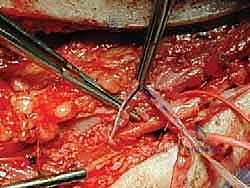

الخلاصة الطبية السريعة: التهاب الأعصاب الالتصاقي (Adhesive Neuritis) هو حالة طبية معقدة ومؤلمة للغاية، تنتج عن تندب الأعصاب الطرفية والتصاقها بالأنسجة الرخوة المحيطة بها، مما يفقدها القدرة على الانزلاق الطبيعي أثناء الحركة. تحدث هذه الحالة غالبًا كمضاعفات لجراحة سابقة، أو نتيجة صدمات وإصابات مباشرة. يتضمن بروتوكول العلاج المتقدم، والذي يقدمه الأستاذ الدكتور محمد هطيف في صنعاء، تحرير العصب جراحيًا بدقة ميكروسكوبية متناهية (Neurolysis)، مقترنًا بإجراءات حاجزية مبتكرة (Barrier Procedures) لتغليف العصب ومنع تكرار تكوّن الالتصاقات، مما يوفر راحة جذرية ودائمة للمرضى ويعيد لهم جودة الحياة.

يهدف نهجه الجراحي إلى تحرير هذه الأعصاب بدقة عالية باستخدام تقنيات الجراحة المجهرية، وفي كثير من الحالات، تطبيق "إجراءات حاجزية" (Barrier Procedures) مبتكرة لمنع عودة الالتصاقات مستقبلاً. يتطلب هذا النوع الدقيق من الجراحة صبرًا استثنائيًا، دقة متناهية، أمانة طبية صارمة، وفهمًا عميقًا للتشريح الإقليمي الدقيق للطرف السفلي، وهي السمات المهنية التي تميز مسيرة الأستاذ الدكتور محمد هطيف.

بينما يمكن أن يتأثر أي عصب طرفي في الطرف السفلي، يعتبر العصب الظنبوبي الخلفي (Posterior Tibial Nerve) هو الأكثر عرضة لهذه الحالة، خاصة بعد جراحة سابقة لتحرير النفق الرسغي للقدم (Tarsal Tunnel Syndrome). ففي بعض الأحيان، يمكن أن تؤدي الجراحة الأولية—التي كان هدفها تخفيف الضغط عن العصب—إلى دورة شرسة من النزيف الداخلي المجهري، الالتهاب، وتكوين الندوب لاحقًا، مما يؤدي إلى انحباس العصب بشكل أسوأ من الحالة الأصلية التي سعينا لتحريرها.